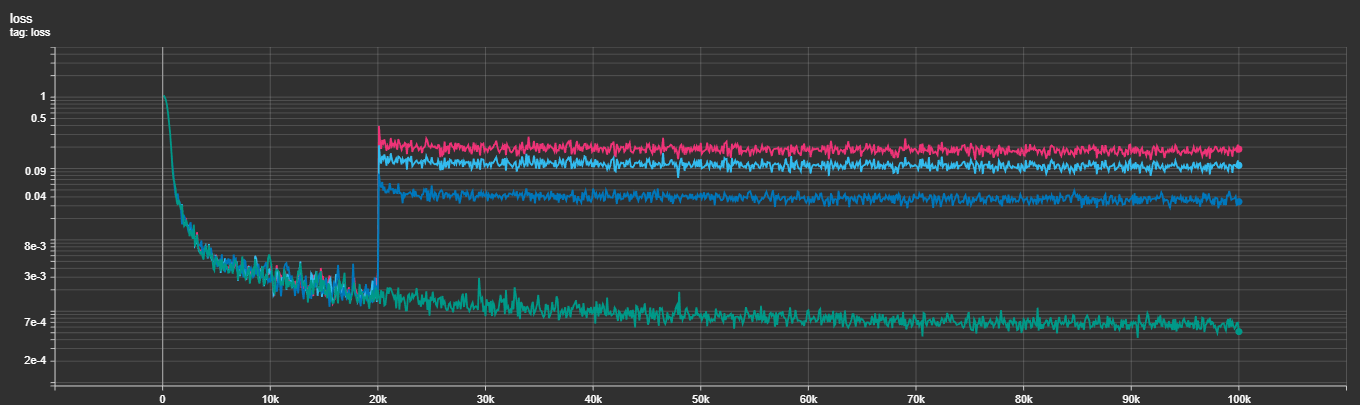

The integration of Multi-Task Losses hasn't been exactly the smoothest, take a look:

As you can see in the figure above, it's very obvious that adding the other losses (at several different weightings) results in the loss jumping multiple orders of magnitude and never quite declining the same. I'm still experimenting with this, with ideas being learned weightings to the losses, different warm-in strategies and others. It's still open.

I've started added gradient accumulation, I'm currently using a physical (on-GPU) batch size of 4. This apparently could be a reason for my metrics not trending upwards beyond what appear to be a random oscillation around the 5.0-6.5% Dice.

It stands that I could experiment around a bit with gradient accumulation till I figure out if indeed that's the source of my issues. If it is, I'll start scaling my runs to actually run the necessary batch size in a single go on multiple GPUs, but I need to see some indication.

The direction forward is still open: I'm experimenting with the training hyperparameters (learning rate scheduler, rate, batch size, augmentation) as well as with the model architectural hyperparameters and loss functions while currently remaining bound to the MedSegDiff architecture that we started our experiments out with. I'm planning to expand to other architectures the moment I start catching a signal and figuring out what combination of parameters would lead to results starting to catch on.